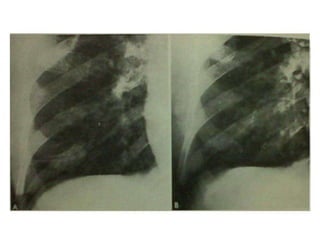

Tuberculoma: It appearsRound or oval, sharply circumscribed nodule that is seldom more than 4 cm in diameter. Central calcification and satellite lesions are common, as is calcification of hilar lymph nodes. This X-ray shows :Single smooth, well-defined pulmonary nodule in the left upper lobe. In the absence of a central nidus of calcification, this appearance is indistinguishable from that of a malignancy.

TUBERCULOMA:(A) Frontal and(B) lateral views of the chest show a large left lung soft-tissue mass (arrows) containing dense central calcification